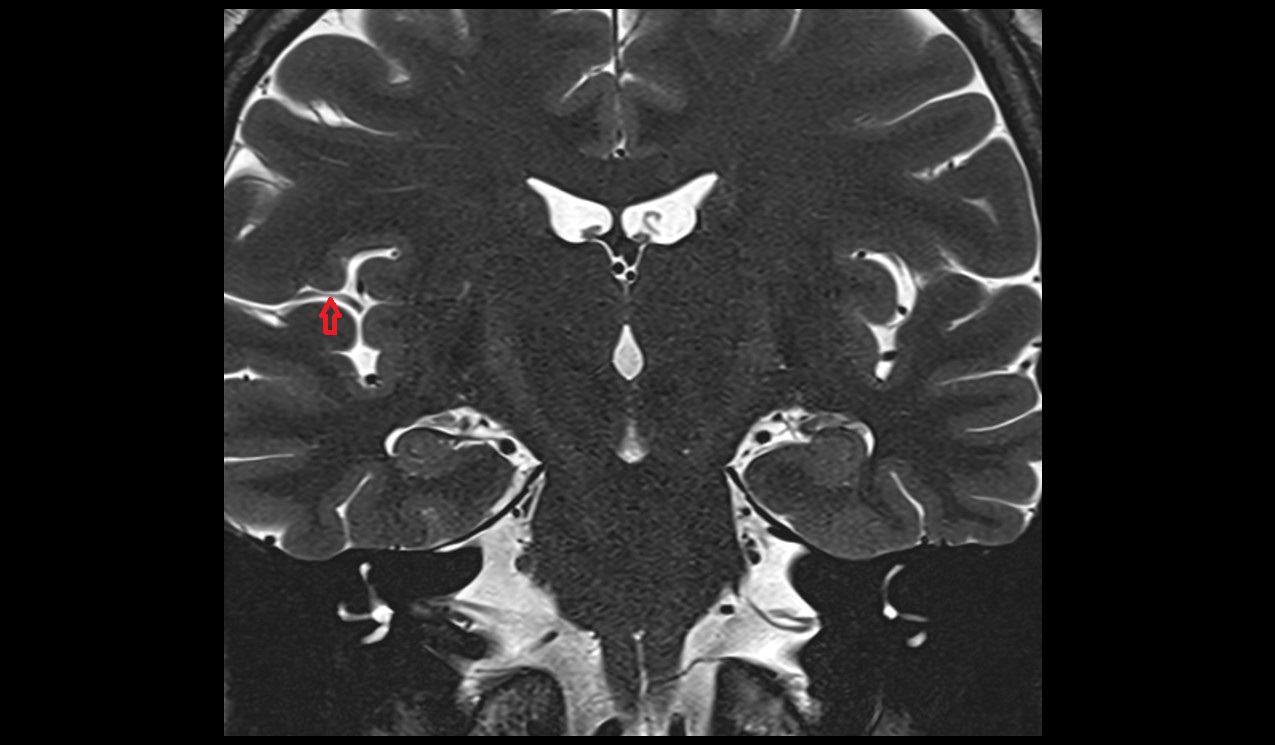

- Hippocampal head

- Head of hippocampus